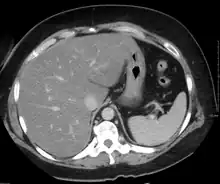

Imaging studies are often obtained during the evaluation process. Ultrasonography reveals a "bright" liver with increased echogenicity. Pocket-sized ultrasound devices might be used as point-of-care screening tools to diagnose liver steatosis. [30] [31] Medical imaging can aid in diagnosis of fatty liver; fatty livers have lower density than spleens on computed tomography (CT), and fat appears bright in T1-weighted magnetic resonance images (MRIs). Magnetic resonance elastography, a variant of magnetic resonance imaging, is investigated as a non-invasive method to diagnose fibrosis progression.[32] Histological diagnosis by liver biopsy is the most accurate measure of fibrosis and liver fat progression as of 2018.[8] Conventional imaging methods, such as ultrasound, CT and MRI, are not specific enough to detect fatty liver disease unless fat occupies at least 30% of the liver volume.[33]